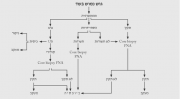

| 11:55, 7 בספטמבר 2012 | TNM123.png (קובץ) |  |

51 קילו־בייטים | Motyk | 1 | |

| 11:58, 7 בספטמבר 2012 | TMNgraph412.png (קובץ) |  |

340 קילו־בייטים | Motyk | 1 | |